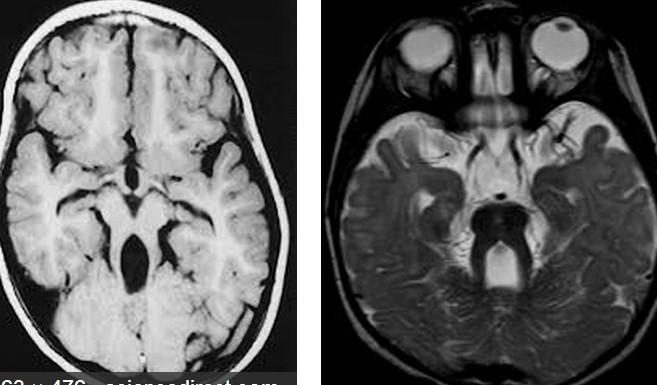

Differential for “cyst in the posterior fossa” starts with whether the vermis is normal or not.

Is the vermis normal? Can you identify the normal structures of the Vermis?

Malrotated hypoplastic vermis, with vertical primary fissure.

“OPEN” fastigial point of the fourth ventricle. Hypoplastic cerebellar hemispheres.

Enlarged posterior fossa

Cystic dilatation 4th ventricle

Uplifted tentorium, TSV sinus, torcula

“torcula-lambdoid inversion” with torcula above the lambdoid suture

Agenetic or hypogenetic vermis with “vermian tail, pushed upward

Cerebellar hypoplasia

CC anomalies 32%

Hydrocephalus up to 90%

Aqueductal stenosis

4th ventricle outlet obstruction

Polymicrogyria, heteropia 5-10%

Occipital Meningo-Encephaloceles 16%

Syndromic = Extracranial anomalies 50%